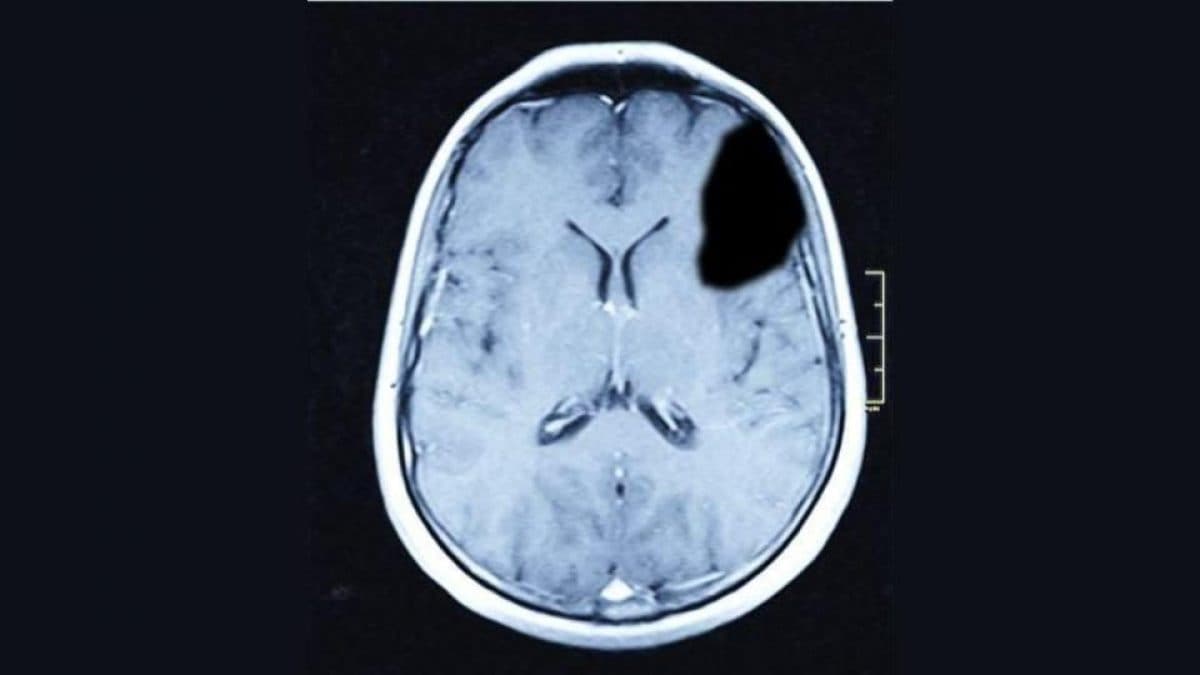

A differenza del passato, però, questa volta qualcosa era cambiato. Le neuroscienze e le tecniche di imaging cerebrale avevano raggiunto uno sviluppo tale da permettere un’analisi dettagliata del cervello, della sua struttura e attività metabolica. Weinstein fu quindi sottoposto ad esami di PET (tomografia a emissione di positroni) e risonanza magnetica (RM), che permettono rispettivamente di osservare la funzionalità e la struttura del cervello. I risultati furono impressionanti: il lobo anteriore sinistro era completamente coperto da una cisti dalle dimensioni di un’arancia, che ne aveva compromesso il normale funzionamento. Questa evidenza biologica era perfettamente coerente con il comportamento insolito esibito dall’uomo. Il lobo anteriore, infatti, svolge un ruolo cruciale nel controllo delle emozioni, nell’inibizione dell’impulsività e nelle capacità di giudizio (ovvero la capacità di valutare le situazioni, prendere decisioni consapevoli e prevedere le conseguenze delle proprie azioni), tutte funzioni evidentemente alterate in Weinstein.